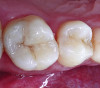

Figure 7. The occlusal outline was extended only to include carious enamel, provide access to the carious dentin, and remove any residual amalgam staining.

Figure 7